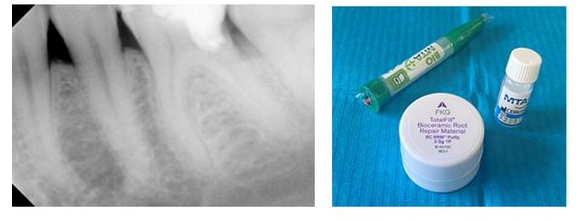

H γνώση και ευαισθητοποίηση για τη σημασία και την αξία της διατήρησης της ζωτικότητας του δοντιού, μας οδηγεί ΣΗΜΕΡΑ σε μία πιο συντηρητική –αναγεννητική αντιμετώπιση των παθήσεων του πολφού. Έτσι σε περιπτώσεις μεγάλου τερηδονισμού ή τραυματισμού δοντιού, στοχευόμενα δεν καταφεύγουμε αμέσως σε ενδοδοντική θεραπεία (απονεύρωση) αλλά εφαρμόζουμε πιο συντηρητικές θεραπείες (άμεση-έμμεση κάλυψη πολφού, μερική – ολική πολφοτομή) με σκοπό να διατηρηθεί το δόντι ζωντανό. Η χρήση των νεότερων βιοκεραμικών υλικών (ΜΤΑ, BIODENTINE) αποτελεί θεραπεία εκλογής σε αυτές τις συντηρητικότερες προσεγγίσεις.

Αρχική εικόνα δοντιού

Τελική εικόνα δοντιού μετά από θεραπεία